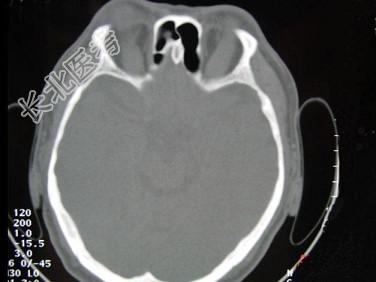

- 单项选择题女,50岁, 消瘦、多饮多食,脖子粗大, 双侧眼球突出1年余,CT检查如图所示, 应考虑为 ( )

A、眼型格氏病

B、甲状腺眼病

C、炎性假瘤

D、横纹肌肉瘤

E、眶部结核